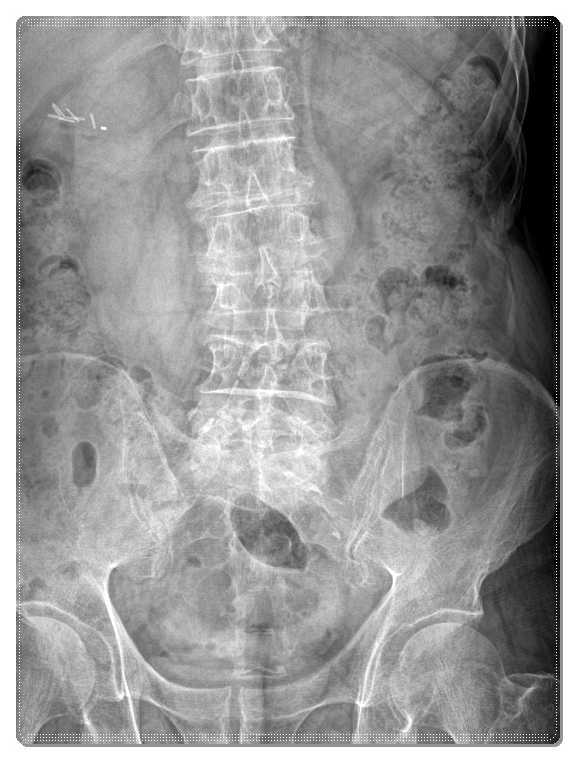

골반은 우리 몸의 중심 구조라서 한 번 골절이 생기면

고관절 주변 움직임에도 큰 제한이 생기게 됩니다.